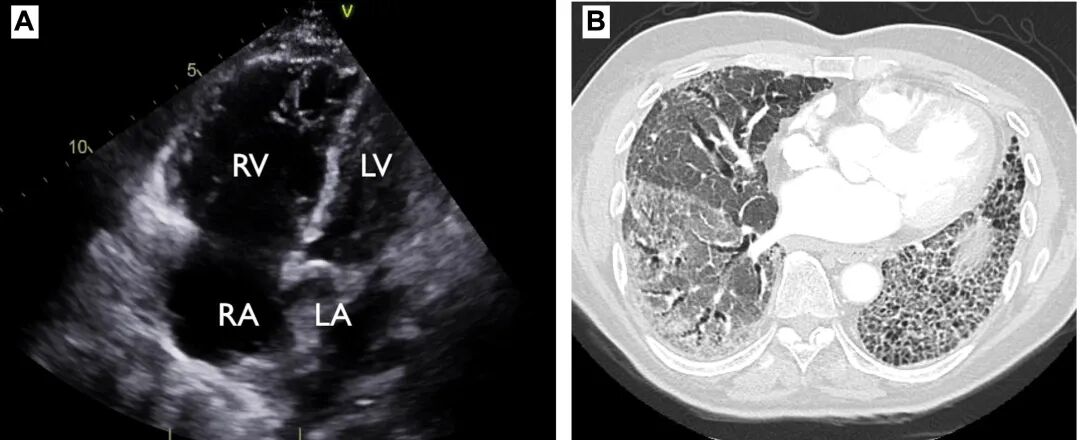

图1 初始诊断检查。(A)经胸超声心动图心尖四腔心切面代表性图像,显示右心房(RA)与右心室(RV)增大;(B)高分辨率胸部CT代表性图像,显示以肺底部为主的磨玻璃影,以及外周胸膜下网状影伴蜂窝样改变。

筛查层面,TTE在ILD人群中存在现实困难:受声窗影响、反流束谱不易评估,RVSP在多达50%患者中可能无法测量;即使可测,估算RVSP与血流动力学测得的肺动脉收缩压相关性也较差。提示重度PH可能性的TTE线索包括:右心形态异常(如RA面积>18 cm²、RV扩大、RV/LV舒张末径比>1、LV偏心指数>1.1等)或RV功能受损(主观评估或以TAPSE、RV面积缩短分数等客观量化)。CT影像也可提供提示(如肺动脉直径>2.9 cm、肺动脉/主动脉比>1、RV扩大与肥厚)。BNP/NT-proBNP与肺动脉压力及预后相关,可用于筛查,但特异性不足,左心衰、肾功能异常或ILD急性加重等亦可升高。

结合本例,多项线索提示存在潜在PH:进行性劳力性呼吸困难;DLCO下降与限制性程度不成比例;CT肺动脉增粗;TTE右心腔室扩大;BNP升高。但考虑到部分检查可能发生在“病毒后ILD加重”阶段,需在加重缓解后复测TTE与6MWT以进一步确认与分层。